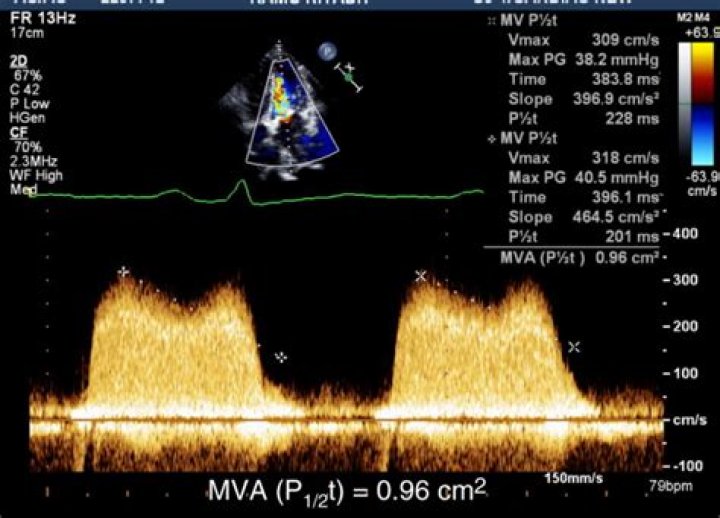

How does PHT measure MVA?

The PHT of the mitral inflow deceleration slope was determined from the stored mitral inflow Doppler VTI, and the MVA was then calculated using the following formula: MVA = 220/PHT (Figure 1) [10].

How do you calculate PHT?

The time from the Vmax to the velocity equal to Vmax divided by 1.4 is the pressure half time. (Vmax / 1.4 is equivalent to the half pressure). 220 divided by the PHT is the mitral valve area.

Calculation of the pressure half-time (PHT) is achieved by measuring the time from peak E wave velocity (V1) to the point when velocity equals peak velocity × 0.71 (V2) (calculations in white) and by measuring the deceleration time from the extrapolated E–F slope and multiplying by 0.29 (calculations in yellow) (D).

Doppler echocardiography is useful in assessing the severity of obstructive cardiac lesions, such as mitral valve stenosis. The Doppler study can be used to calculate pressure half-time (PHT), which is defined as the time required for the pressure gradient across an obstruction to decrease to half of its maximal value.